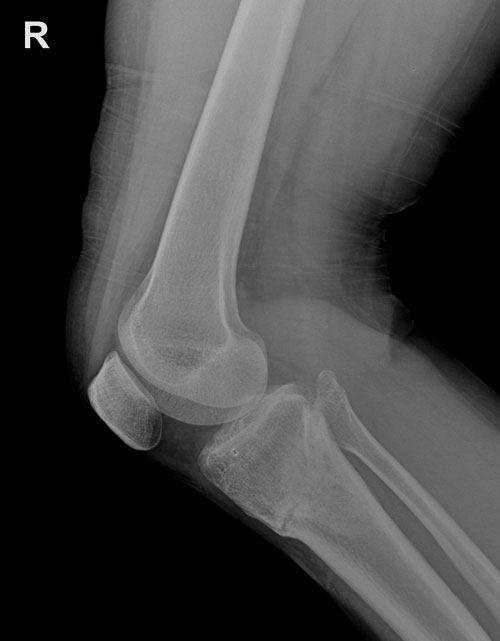

Мне 36 лет. Живу в Алматы, замужем, есть ребенок. Казалось бы все хорошо, да вот только с ногами не очень повезло. Я большой любитель ходить пешком. Для меня это одновременно и отдых и физическая нагрузка. Только, в последнее время стала замечать боли в области колен, когда преодолевала сравнительно небольшие расстояния. Были подозрения, что это возможно первоначальная стадия артроза. К тому же, меня расстраивало некрасивые форма ног (О-образная), которую приходилось прятать под брюками. Выбрать "правильную" одежду для меня всегда было не из самых приятных моментов. И вот я решила закрыть данную проблему кардинально. Прочитала много тем, предложений и отзывов по профилактике артроза и исправлению кривизны ног. Была на консультации у нескольких врачей. Но в глубине души все равно оставались сомнения... Продолжила поиски. В один прекрасный день вышла на сайт клиники Онипко. Изучила всю информацию на сайте, а также многолетний опыт доктора Онипко. Окончательное решение приняла сразу и бесповоротно. И только в пользу нашего многоуважаемого доктора Николая Николаевича Онипко! Предварительно созвонившись с секретарем Онипко, утром 21 марта приехала в клинику, сдала все необходимые анализы, сделали рентген снимок. Операция была назначена на следующий день. Я была готова и морально и физический. Операция прошла удачно. В первый день отходила от наркоза. Смогла встать на второй день после ОП утром. Спустила ноги, даже получилось по палате передвигаться.

Вот и настал тот долгожданный и трепетный момент. Сделала рентген в 90 дней. Осмотрев снимок Николай Николаевич, сказал, что уже можно снимать аппараты. В тот день он ослабил болтики, а сняли аппараты на следующий. Перед снятием аппаратов не принимала никаких обезболивающих средств. Я была готова на худшее. Но это действительно было не так страшно. Скорее больше страха в ожидании боли. Да и что скрывать, мой болевой порог высокий. Не знаю это плюс или минус... Происходило это следующим образом: сначала раскрутили болтики, дальше было обкусывание спиц и в конце их вытаскивание. Последние два этапа смотреть я не стала. Было немножко неприятно. Вся процедура заняла максимум 5-8 минут. Так что, по моему мнению, это короткая и вполне терпимая боль. Думаю, что столько перенесли после операции (заново учиться делать свои первые шаги, ходить, крутки, ротация и т.д.), то можно с достоинством, стиснув зубы, потерпеть завершающий этап на пути к красивым ножкам .

Дата операции 22.03.2016г.

Дата снятия аппаратов 22.06.2016г.

Срок лечения 90 дней.

Рентген контроль в 1,5 месяца после снятия аппаратов.

Сращение отличное! Разрешено всё по нарастающий ( имея ввиду нагрузку). Каблуки разрешены, фитнес разрешён.